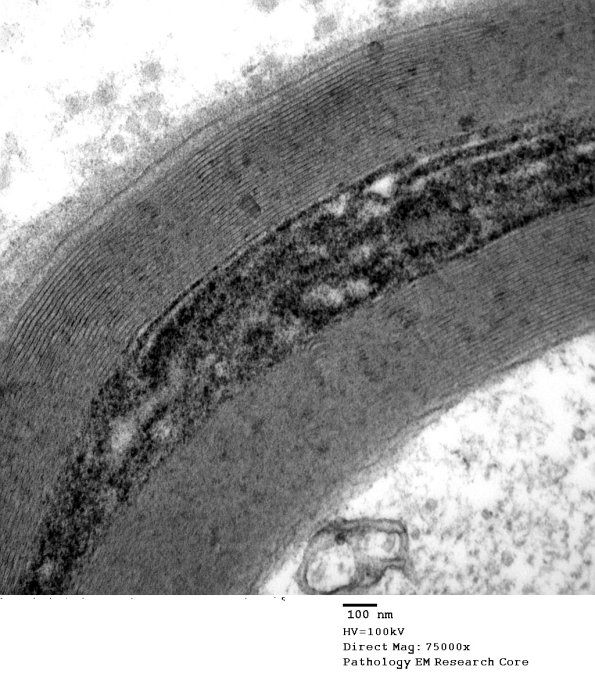

Washington University Experience | PERIPHERAL NEUROPATHY | 3 NORMAL MYELIN & SCHWANN CELLS | 3 Schmidt-Lanterman Clefts | 10B4 S-LC (Case 10) EM 158 - Copy

10B4 S-LC (Case 10) EM 158 - Copy

Higher magnification of image #10B1. (electron micrograph)